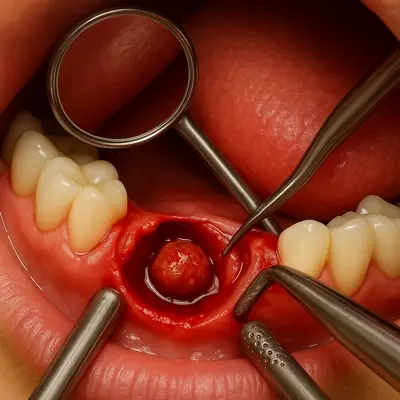

جراحی ریشه دندان (اپیکوکتومی)

اگر درمان عصبکشی نتواند عفونت را بهطور کامل از بین ببرد، جراحی ریشه دندان یا اپیکوکتومی انجام میشود.

در این روش، دندانپزشک جراح از ناحیهی لثه وارد میشود و بخش عفونی نوک ریشه را حذف میکند. این عمل مانع از گسترش التهاب در استخوان فک میشود و در حفظ دندان نقش حیاتی دارد.